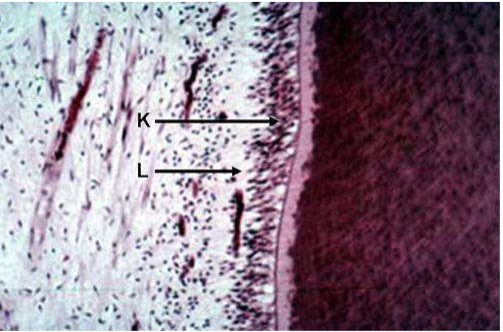

科目:牙醫學(一)(包括口腔解剖學、牙體形態學、口腔組織與胚胎學、生物化學等科目及其臨床相關知識) | 年份:105年 | 選擇題數:80 | 申論題數:0

所屬科目:牙醫學(一)(包括口腔解剖學、牙體形態學、口腔組織與胚胎學、生物化學等科目及其臨床相關知識)